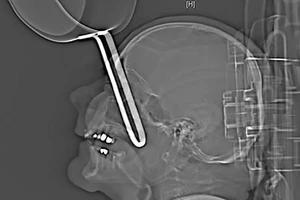

Nam thanh niên bị thanh sắt đâm xuyên cổ vẫn tỉnh táo